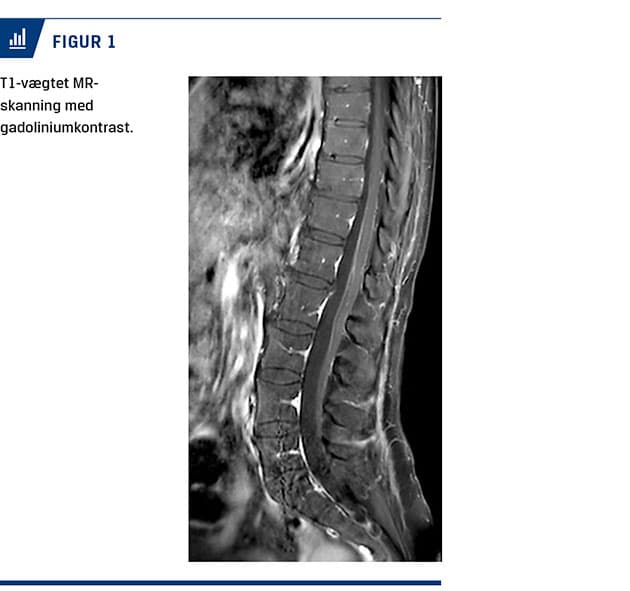

Ved en objektiv undersøgelse fandt man nedsat kraft i alle fire ekstremiteter, men mest udtalt i benene og særligt over hoften uden supranukleær fordeling. Der blev fundet ataksi trunkalt og i ekstremiteterne. Senereflekser var fraværende, og plantarresponset var normalt. Sensibiliteten var bevaret, men med allodyni distalt i underekstremiteterne. Kranienerverne var upåvirkede. Undersøgelse af cerebrospinalvæsken (CSV) viste mononukleær pleocytose på 90 × 106/l kerneholdige celler (referenceværdi: < 5 × 106/l) med 91% mononukleære leukocytter, moderat forhøjet proteinniveau på 3,23 g/l (referenceværdi: 0,15-0,50 g/l) og glukoseniveau på 3 mmol/l (referenceværdi: 2,2-3,9 mmol/l). Gentaget efter to og tre uger var der nærnormalisering af celletællingen og let forhøjet proteinniveau. Gentagne undersøgelser for herpes simplex-virus-1 og -2, varicella-zoster-virus, hiv, syfilis, hepatitis E og borrelia var negative. En polymerasekædereaktion (PCR) for TBE i CSV var negativ. Initiale serologiske undersøgelser for TBE-antistoffer i oktober var positive for immunglobulin (Ig)M, men ikke for IgG. Da undersøgelserne blev gentaget efter fire uger, var patienten positiv for IgM og IgG. En MR-skanning med kontrast af columna viste leptomeningeal kontrastopladning ved conus medullaris og filum terminale (Figur 1). En nerveledningsundersøgelse (NLU) viste svært nedsatte motoriske amplituder, moderat nedsatte sensoriske amplituder og nedsatte nerveledningshastigheder i alle fire ekstremiteter uden affektion af nn. suralis.

This is a case report of a 68-year-old woman, who developed malaise after an insect bite. Symptoms subsided, and over weeks progressing difficulty with walking, ataxia and universal areflexia developed. A lumbar puncture showed mononuclear pleocytosis and moderately raised protein levels with no detected viral agents. An MRI of the spinal cord showed leptomeningeal contrast attenuation distally. Serum samples were positive for anti-tick-borne encephalitis (TBE) IgM-antibodies, but not IgG, and showed seroconversion. TBE is endemic in areas of Central Europe and Scandinavia but has earlier only been shown in the eastern part of Denmark.